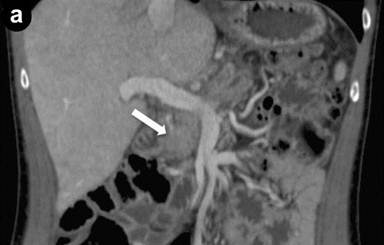

A 43-year-old man referred to us for abdominal pain and weight loss. IgG4 levels were elevated (298 mg/dL). Coronal scans with contrast enhanced CT (Image 3ab) showed the pancreatic head was enlarged with hypodense areas (2.7 cm, arrow) without vascular involvement of the mesenteric vessels. The pancreatic duct was dilated in both the body and the tail regions (arrowhead); the biliary tree was normal. The CT scan findings suggested pancreatic cancer. EUS and EUS-FNB were requested. Linear scanning (Image 3c) showed an enlarged pancreatic head with a focal hypoechoic mass (22 mm measured with calipers) with irregular margins (arrowheads). Upstream dilatation of the main pancreatic duct (8 mm, measured with calipers) in the body-tail regions was associated with the echopoor focal lesion (arrowheads); the lesion had close contact with the superior mesenteric vein (Image 3d). On EUS Doppler study (Image 3e), the echopoor lesion of the pancreatic head (arrowheads) appeared hypovascular; the superior mesenteric artery (arrow) and vein were patent.